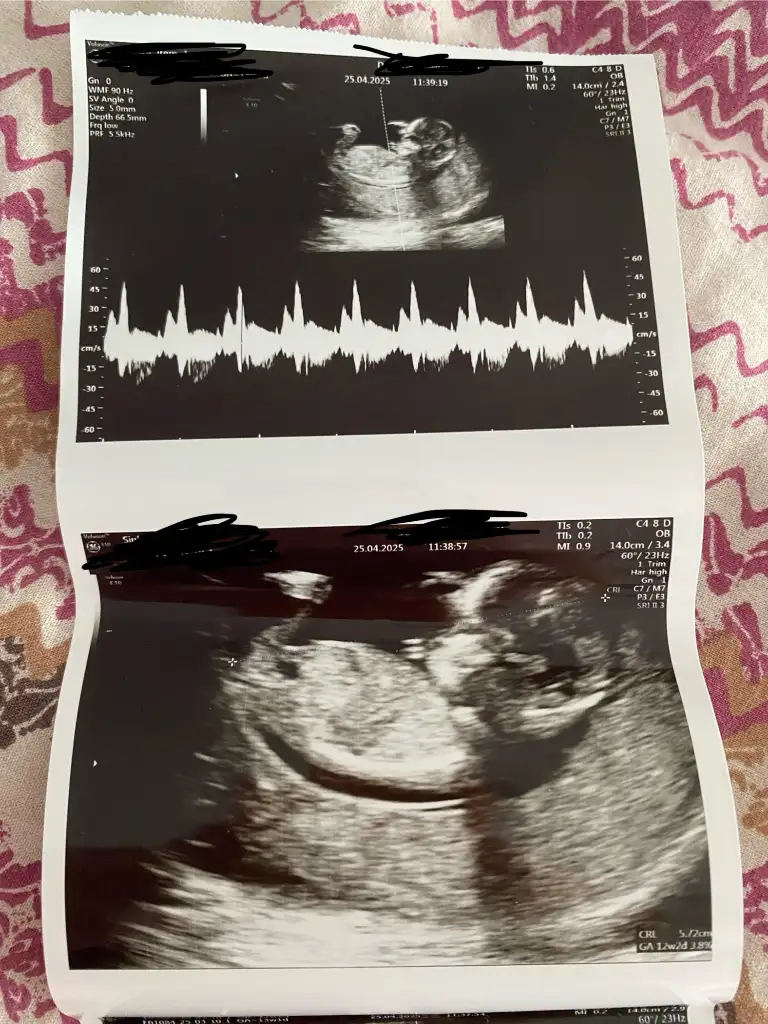

Kese şekli erkeğe benziyor ama, Allah bilirSizce cinsiyet nedir 12 haftalık

Kıza benziyor, kesenin yuvarlak olması kız fasulye tipi erkek diyorlar ona istinaden13 haftalık anlayan varmı ?